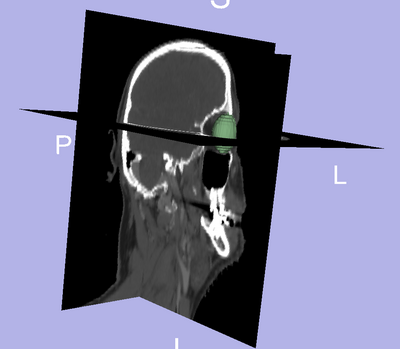

- We are interested in segmenting the eye ball, lens, optic nerve, and the optic chiasm.

- The eye ball is considered to be the pivotal organ since its segmentation will localize the region of interest when looking for other structures.

- We segmented the eye ball.